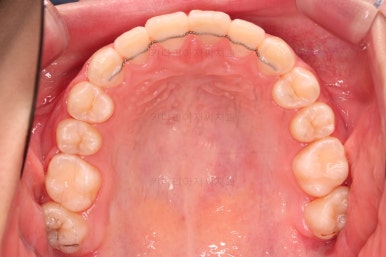

✅ 악궁 확장

악궁확장 내용이 나올 때면 매번 말씀 드리는 내용이 있습니다.

치열이 삐뚤었다고 공간확보 목적으로 악궁확장을 하는 건 아니다.

아래와 위의 턱뼈의 크기 부조화가 있을 때 위턱을 넓혀주는 것이 악궁확장이며, 저희 부산청소년교정치과 키다리아저씨치과에서는 정교한 3차원 CT분석을 이용해서 골격의 크기를 비교해서 꼭 필요한 경우에 악궁확장을 해주게 됩니다.

당연히 확장을 하면 부가적으로 공간확보가 일정 부분 더 잘된다는 효과도 있지만 공간확보를 위해서 턱뼈의 크기가 조화로운데도 불구하고 악궁확장을 한다면 또 다른 좋지 못한 결과가 생길 수 있어서 매우 조심스러운 평가가 선행되어야 합니다.

이번 환자분은 악궁확장이 필요한 케이스였으며, 청소년이었기 때문에 별도의 미니스크류 없이 일반 확장장치를 이용했습니다.

악궁확장부터 시행합니다.

확장이 잘 되어 앞니 사이에 틈새도 잘 벌어진 것이 확인되고요.

종료 때의 사진입니다.

가지런하고, 교합도 좋으며 과개교합이나 앵글씨 2급 부정교합 부분도 완벽히 좋아졌습니다.

자연스럽게 중앙선도 매우 좋아졌고요.